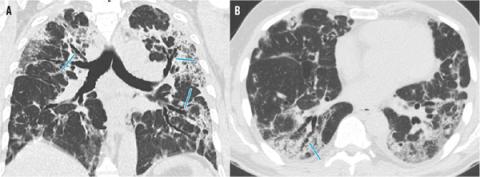

Der blev foretaget højresolutions-CT af thorax efter 28 indlæggelsesdøgn, hvilket gav et blandingsbillede af infiltrative forandringer, både potentielt reversible inflammatoriske infiltrater og mere cikatricielt udseende forandringer. Forandringerne fordelte sig i alle lapper, men var mere udtalte posteriort end anteriort. Områderne med mere cikatricielt udtryk sås med både matglaspræg og tæt konsolideret præg, med eller uden septal fortykkelse, udbredte traktionsbronkiektasier og volumentab. De traktionsbronkiektatiske forandringer strakte sig flere steder langt centralt, men var også udbredte perifert. Spredt i de mere cikatricielt udseende områder lå en del tilsyneladende upåvirkede sekundære lobuli, nogle dog med fokal airtrapping på eksspirationsserien, mens der omvendt tilsyneladende var effektivt luftskifte i flere af de matglasprægede områder. Der var ingen tidligere CT-billeder til sammenligning. Seks år gamle røntgenbilleder af thorax viste normale forhold.

Blandingsbillede med både matglasinfiltrater og mere konsoliderede infiltrater samt moderate og udtalte traktionsbronkiektasier (pile). A. Koronalt snit. B. Aksialt snit.